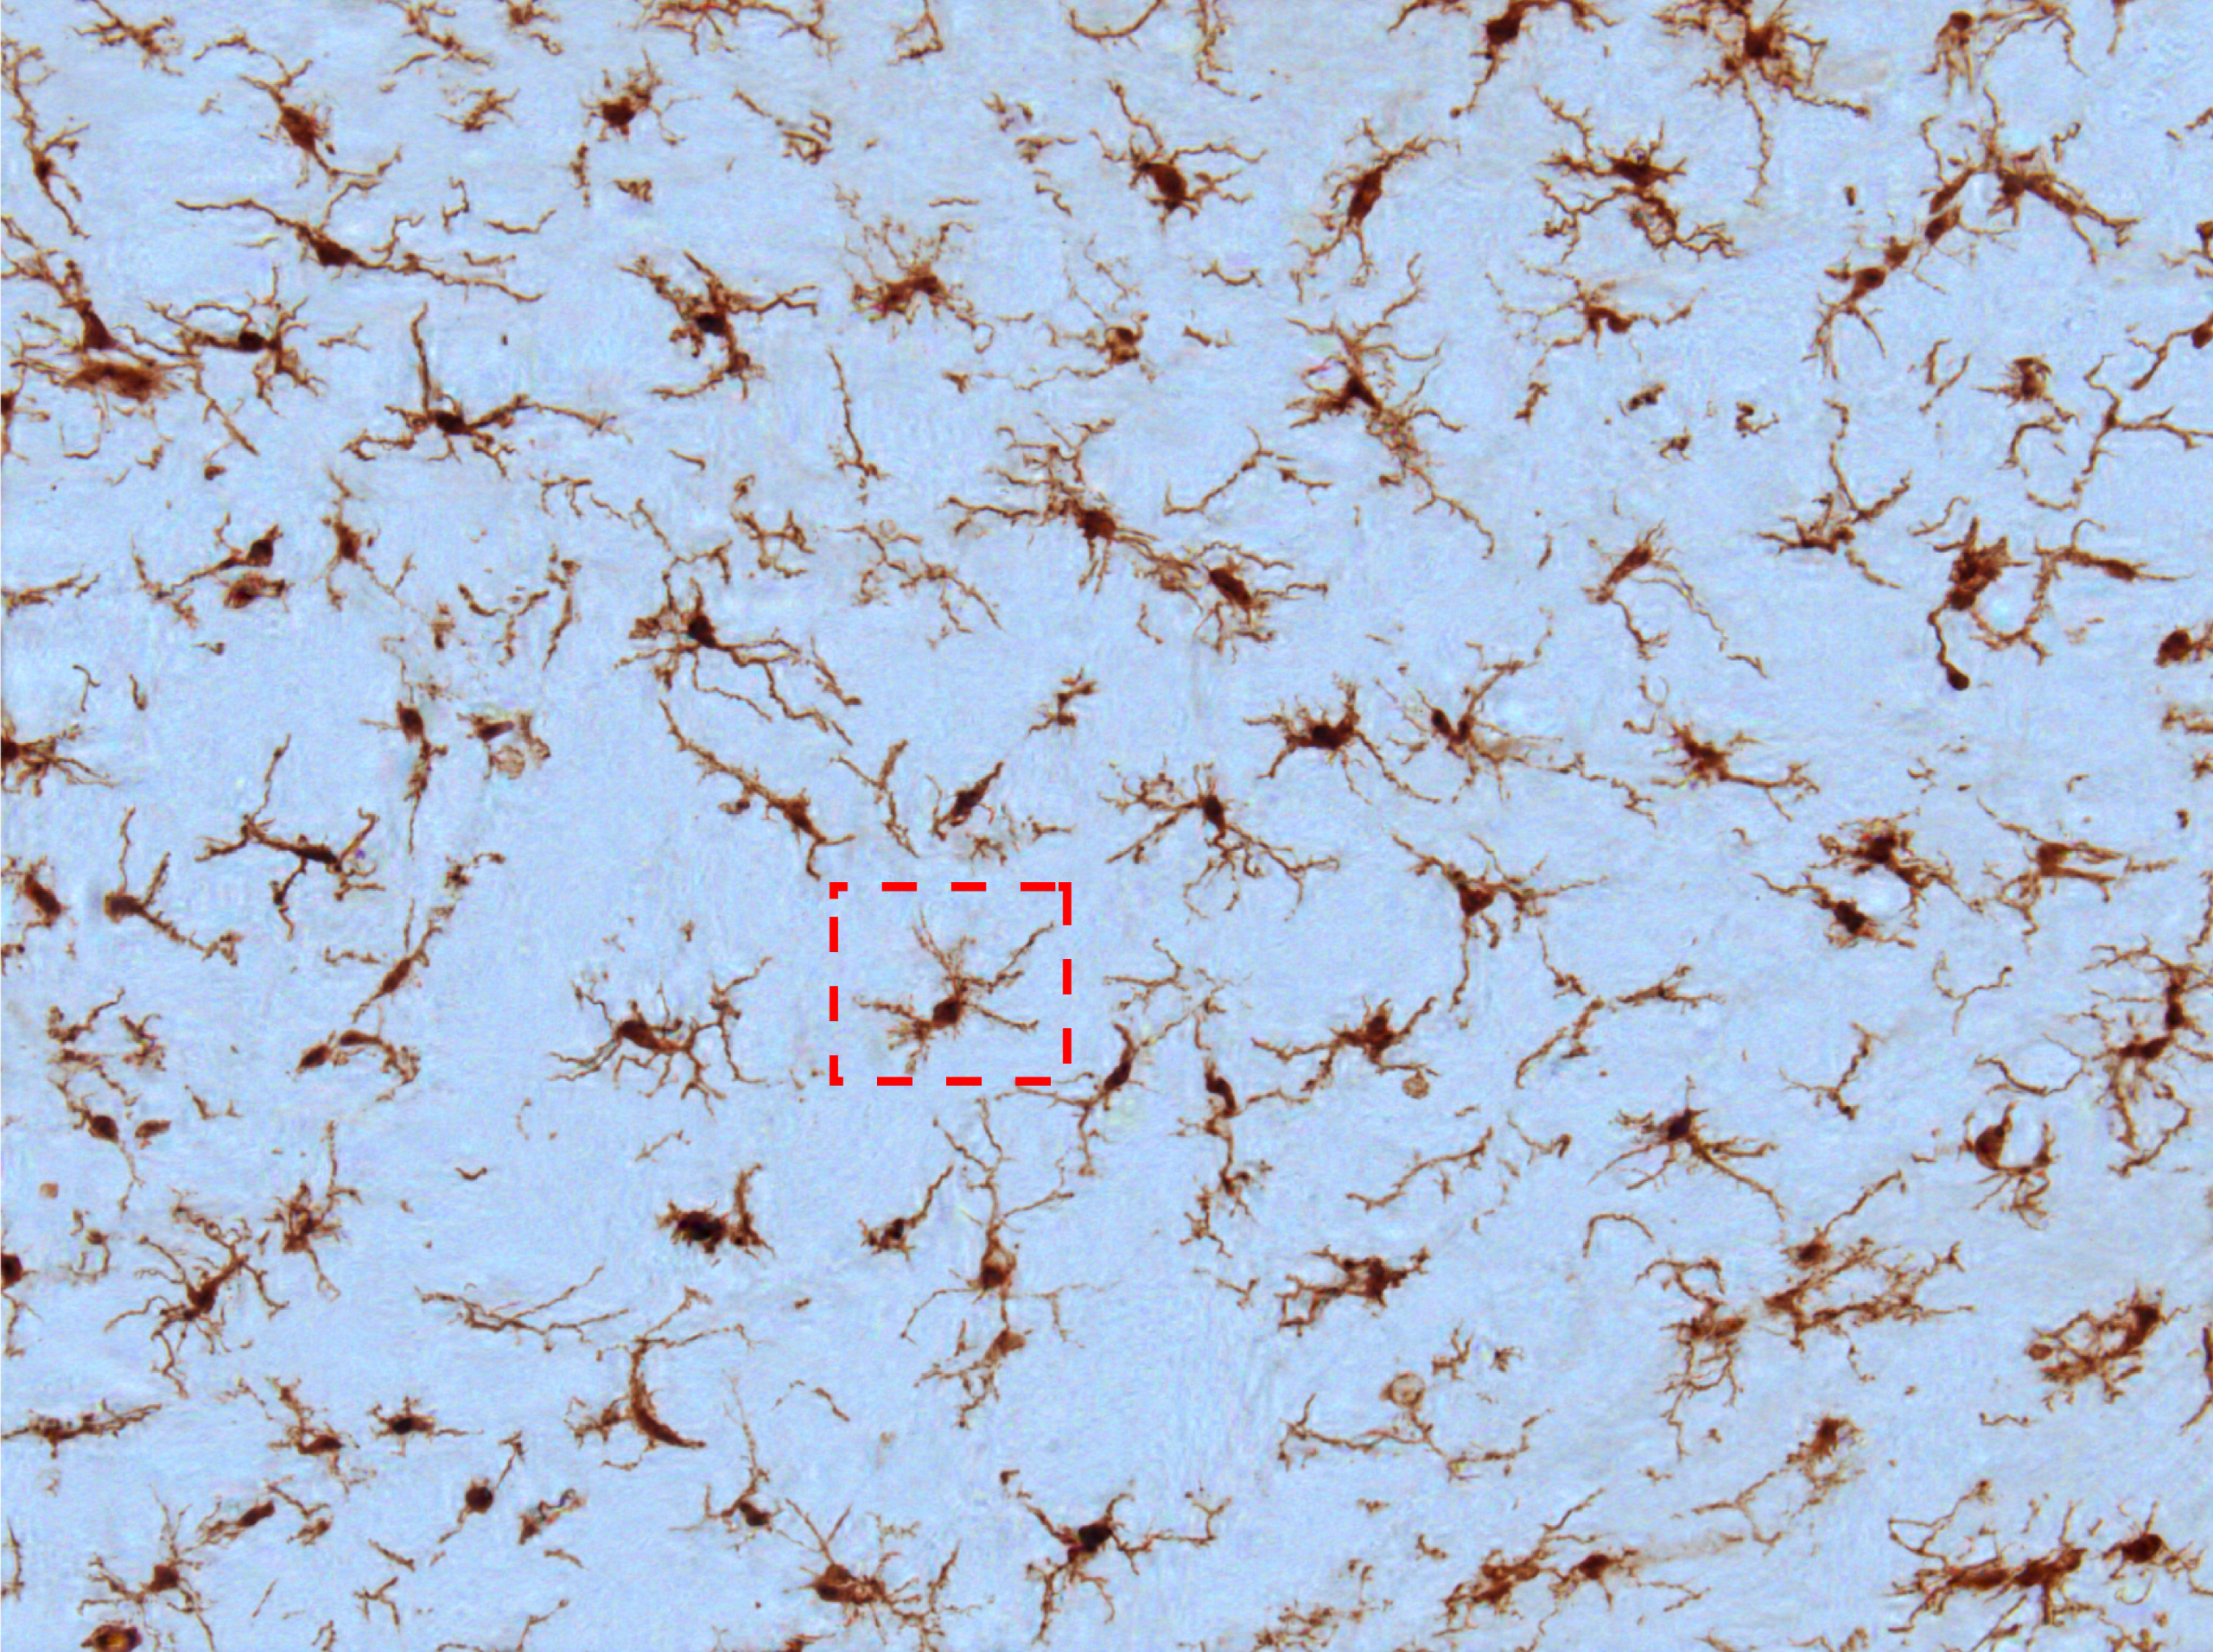

위의 이미지는 Anwer et al., (출처 1) 의 페이퍼에서 제시하는 microglial cell을 기록한 영상파일 입니다. ( 자세한 사항은 본 블로그의 [MATLAB 영상처리 활용] Microglial cell segmentation review를 참조해 주시고, 위의 이미지는 본 블로그 맨밑 출처 1에서 제시하는 이미지로써 이곳에 가셔서 다운로드 받을 수 있습니다. ) 만일 이미지 프로세싱의 목적이 위의 영상에서 microglial cell을 검출(extraction) 하는것이라면, 최종결과 중의 하나로써 검출된 cell(세포)의 위치를 지정된 색상으로 덧입혀 표시하는 결과 이미지일 것입니다. 보통 cell(세포)의 검출에는 black & white mask가 활용되므로 이를 이용해 간단한 예..

[MATLAB 영상처리 활용] Microglial cell extraction/segmentation review - part1

Microglial cell은 뇌신경계에서 일종의 immune cell로 알려져 있으며 최근에 다양한 시각으로 활발한 연구가 진행중입니다. 일반적인 실험/파이프라인 설계는 two-photon 또는 confocal microscope 등으로 microglia immune response의 dynamics 를 이미징 하고나서, 이미지 분석을 통해 의미있는 데이터를 추출하는 순서로 진행합니다. 실험 수행후 수많은 이미지 모음(image-set)을 만들고, 하나의 이미지에서 수많은 유의미한 데이터를 얻을 수 있습니다. 따라서 자동화된 cell 검출 (automatic cell segmentation) 알고리즘/프로그램이 많이 공개되어 왔고 현재에도 계속 발전되고 있습니다. 본 포스트에서는 이미 공개된 micro..